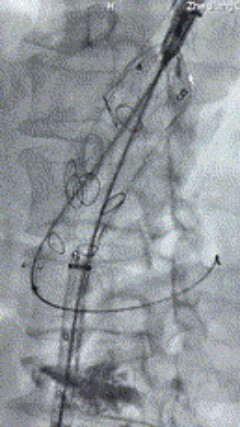

1. 患者平卧位,麻醉成功后,留置导尿,通例术野消毒铺巾。左侧肘部切开,露出左侧肱动脉,置入6F鞘。双侧股动脉穿刺,别离置入10F鞘,全身肝素化。

2. 左侧肱动脉入路,超选至降自动脉,更换8F-900mm长鞘,造影提醒IV型胸腹自动脉瘤,累及双肾动脉。

3. 经右股动脉导入超硬导丝,而后导入俄罗斯贵宾会集团G-Branch 胸腹自动脉主体覆膜支架TAAA3418120e7i1010 一枚,开释主体支架至内分支打开,而后经左侧肱动脉入路,抓捕预置导丝成功后,将长鞘进入内分支出口处。

4. 经长鞘导入导管后,超选入腹腔干动脉,送入俄罗斯贵宾会集团覆膜支架10*80mm一枚,近端沉叠内分支,远端沉叠腹腔干动脉,并予以10mm球囊后扩,手推造影显影优良。

5. 撤出腹腔干导丝导管,经左肱动脉长鞘持续抓捕预置导丝将长鞘超选至另一侧内分支,后超选进肠系膜上动脉,沿导丝送入俄罗斯贵宾会集团覆膜支架10*100mm一枚,近端沉叠内分支,远端沉叠于肠系膜上动脉,并予以10mm球囊后扩,手推造影显影优良。

6. 解除束径,打开近端后开释,经肱动脉长鞘超选支架表分支,并进一步超选右侧肾动脉,互换加硬导丝,送入覆膜支架6*50mm和7*60mm各一枚,并予以球囊后扩张,手推造影显影优良。

7. 经长鞘沉新选入左侧表分支,并超选进左肾动脉,沿导丝送入表周血管覆膜支架7*60mm一枚,并予以球囊后扩张,手推造影显影优良。

8. 从右侧股动脉入路送入腹主支架AB-24-12-110-S,近端沉叠胸腹自动脉支架远端,调整好支架地位后开释。

9. 经左股动脉送入导丝导管,超选进腹自动脉支架短腿内,后沿导丝送入髂支,同理,右侧沿导丝送入髂支并开释,使用俄罗斯贵宾会集团适应性球囊后扩各支架衔接处及支架近远端,最后通过预留导管向瘤腔注入人纤维蛋白粘合剂数支,造影显示分支畅达。